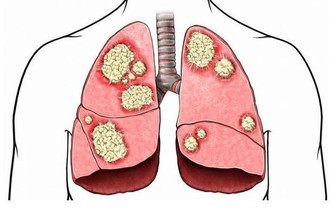

隨著通訊科技發達,現代人生活越來越離不開3C產品,上班族更是要盯著電腦螢幕長達八小時,前往眼科求診的年齡層逐漸下降,用眼過度導致許多青壯年族群,尚未髮蒼蒼就視茫茫,甚至傷害視網膜黃斑部。

現代上班族長時間使用電腦、手機、平板,在不能改變這個現象的前提下,如何保護眼睛遠離黃斑部病變,是民眾應該重視的課題,趙順榮藥師建議,民眾使用3C產品,每30分鐘至50分鐘就需休息,將目光轉移至較遠的景物,此外,也能從飲食上做改變。

靈魂之窗的重要性不言可喻,趙藥師提醒,視力保健應從平常生活習慣調整做起,適度的讓眼睛休息、熱敷及按摩,多攝取天然的蔬果等,若有任何不適,也應立即前往眼科讓醫師診斷治療。